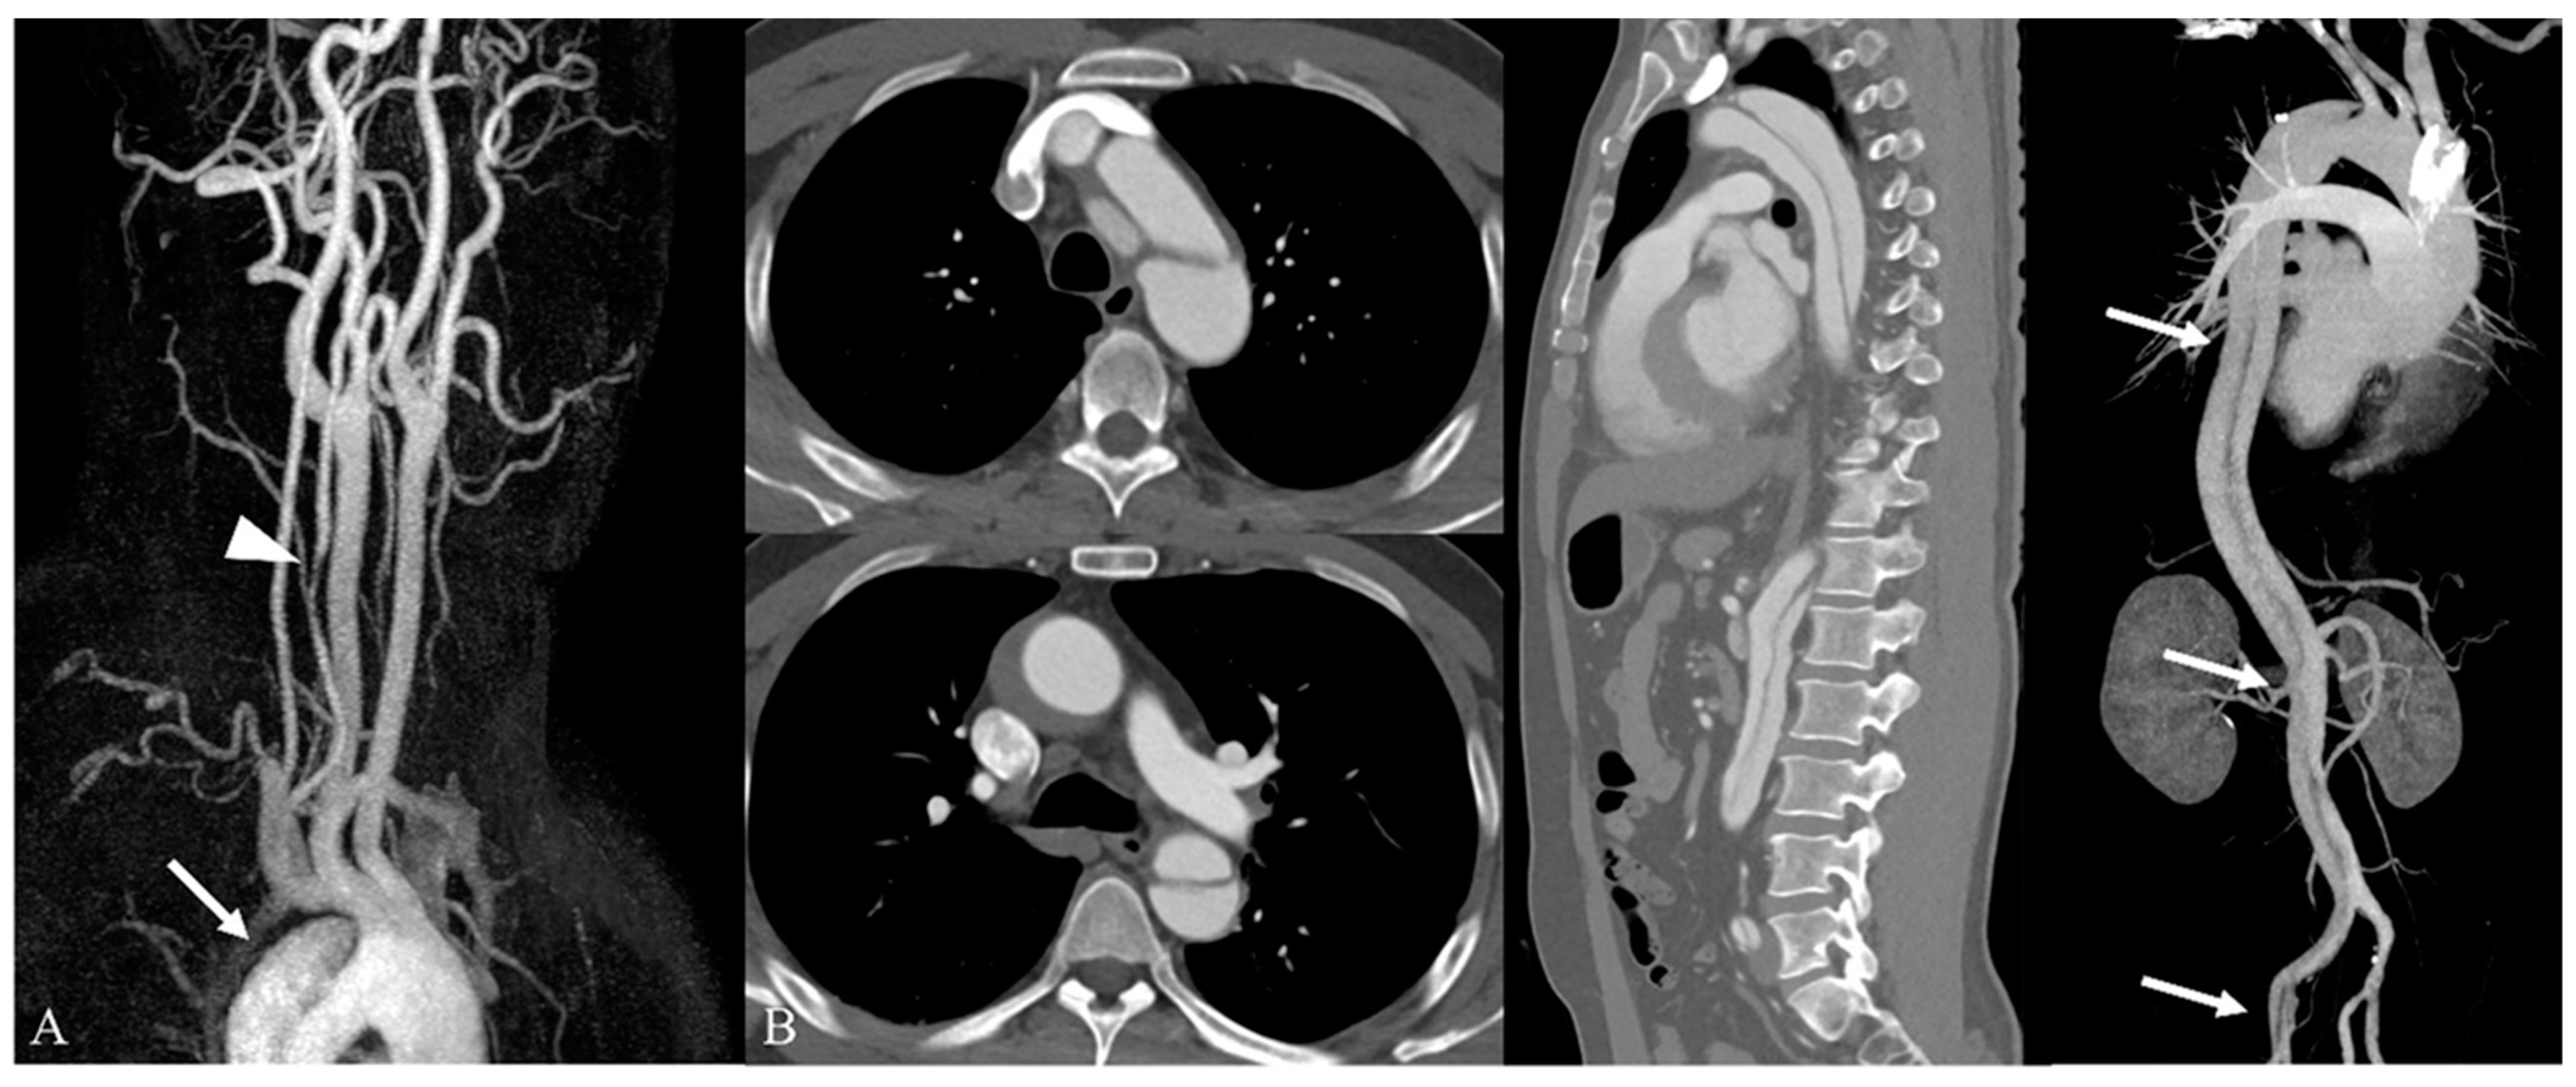

3.2. Incidental Aortic Arch Abnormalities on Contrast-Enhanced Neck MR Angiography

| Category I (Clinically significant findings) | 29/348 (8.3%) | 29/348 (8.3%) |

| Aortic dissection | 22/348 (6.3%) | |

| Aortic aneurysm | 7/348 (2.0%) | |